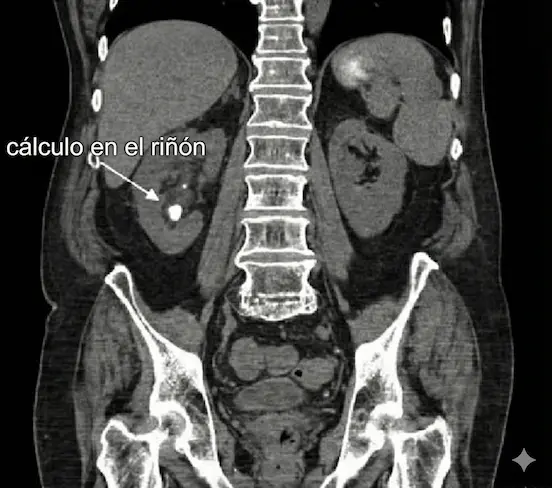

Tomografía (TAC Simple)

El "Gold Standard". La prueba de máxima precisión para ubicar exactamente la piedra, medir su dureza y planificar el tratamiento láser.

La litiasis urinaria, también conocida médica y formalmente como urolitiasis, es la formación de cálculos (depósitos sólidos o "piedras") compuestos por minerales y sales cristalizadas que se agrupan en tu orina.

• Riñones: Lugar principal donde se forman.